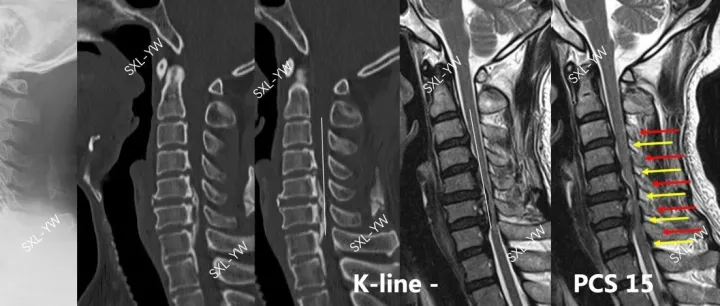

袁文:PCS评分在颈后路椎管扩大椎板成形术中神经功能恢复情况的预测价值

该评分具有预测神经功能恢复情况、指导手术方式选择、明确手术范围的作用。